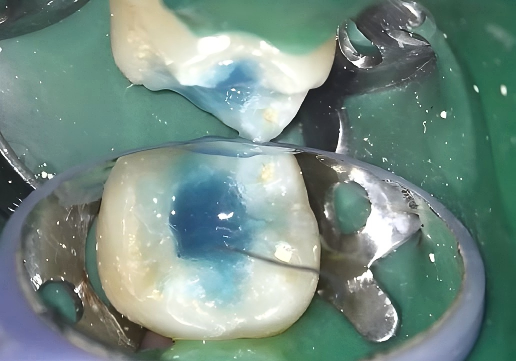

2. Etching

P-Etchant phosphoric acid etchant was applied to enamel and dentin. The surface was thoroughly rinsed and dried to prepare it for bonding.